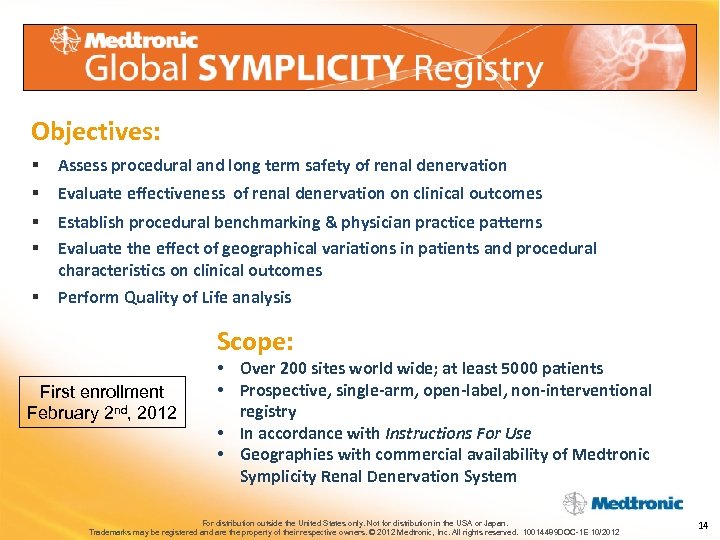

Objectives: § Assess procedural and long term safety of renal denervation § Evaluate effectiveness of renal denervation on clinical outcomes § § Establish procedural benchmarking & physician practice patterns Evaluate the effect of geographical variations in patients and procedural characteristics on clinical outcomes § Perform Quality of Life analysis Scope: First enrollment February 2 nd, 2012 • Over 200 sites world wide; at least 5000 patients • Prospective, single-arm, open-label, non-interventional registry • In accordance with Instructions For Use • Geographies with commercial availability of Medtronic Symplicity Renal Denervation System For distribution outside the United States only. Not for distribution in the USA or Japan. Trademarks may be registered and are the property of their respective owners. © 2012 Medtronic, Inc. All rights reserved. 10014489 DOC-1 E 10/2012 14

Objectives: § Assess procedural and long term safety of renal denervation § Evaluate effectiveness of renal denervation on clinical outcomes § § Establish procedural benchmarking & physician practice patterns Evaluate the effect of geographical variations in patients and procedural characteristics on clinical outcomes § Perform Quality of Life analysis Scope: First enrollment February 2 nd, 2012 • Over 200 sites world wide; at least 5000 patients • Prospective, single-arm, open-label, non-interventional registry • In accordance with Instructions For Use • Geographies with commercial availability of Medtronic Symplicity Renal Denervation System For distribution outside the United States only. Not for distribution in the USA or Japan. Trademarks may be registered and are the property of their respective owners. © 2012 Medtronic, Inc. All rights reserved. 10014489 DOC-1 E 10/2012 14